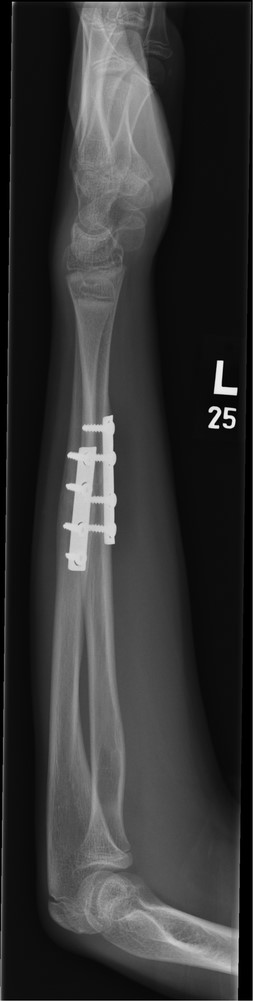

Three months post-operative lateral radiograph showing radiological union.